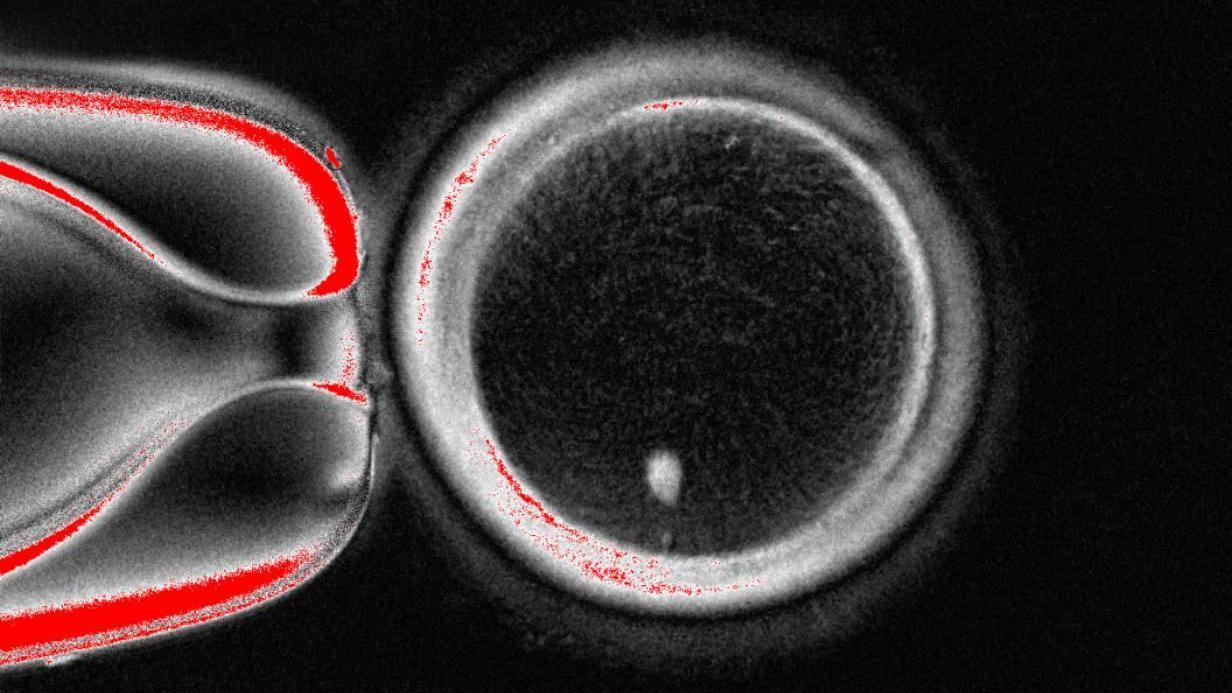

Una imagen en blanco y negro que muestra un objeto redondo. Es oscuro en el centro y presenta una gruesa franja blanca en la circunferencia. Hay un punto blanco brillante en el círculo, en la zona de abajo del círculo.

OHSU

El círculo grande es el óvulo visto bajo un microscopio. El punto blanco en la parte inferior es el material genético tomado de una célula de la piel y colocado dentro.